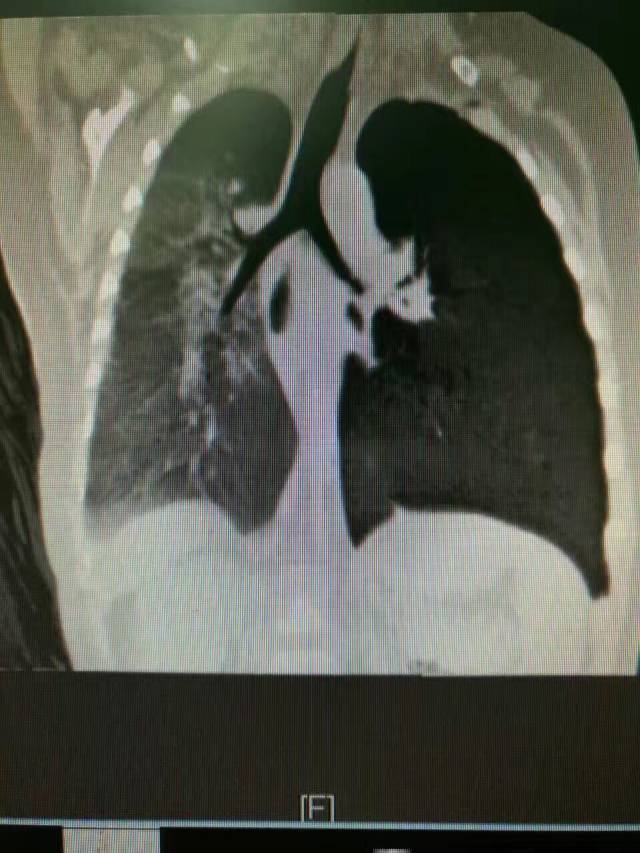

他在朋友圈说:9个月的宝宝反复肺炎3个月,CT提示支气管异物纤维支气管镜下见异物,位于左下叶基底段:

尝试夹取异物未成功,转我科支气管硬镜取出2mm大小的蓝色塑料珠,怀疑为衣服装饰物。